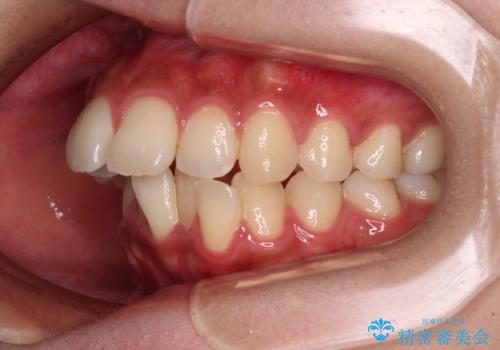

- 前歯の突出感とデコボコを気にして来院された患者様です。

奥歯の噛み合わせをみると、上顎歯列が全体的に前突している状態であり、この咬み合わせのまま歯列を整えると出っ歯になってしまう可能性がありました。

上下の前歯が接触する仕上がりとなったので、横顔の印象が大幅に改善されました。